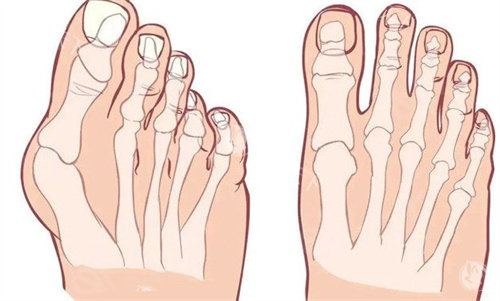

困扰多年的双脚难题

我的双脚大脚趾根部长期以来一直向外突出,形成难看的骨凸。不仅穿鞋经常磨脚,走路时间稍长就会隐隐作痛。每到夏天,我总是避免穿凉鞋,担心别人看到我变形脚型的异样眼光。这种困扰像块沉甸甸的石头压在我的心头,让我渴望找到解决之道。

接诊的医生经验充足且态度和蔼。他仔细检查了我的双脚,让我做了一些简单动作来观察脚部活动情况,还结合X光片详细解释了拇外翻的形成原因和发展程度。这种正规的讲解让我对自己的病情有了清晰认识,也对后续治疗增添了信心。

医院采用的小创口技术切口很小,只有3-5毫米,通过这种微小切口就能祛除骨赘。手术结合了更准矫正和牵引技术,避免了传统截骨手术的一些风险。据了解,这种技术术后24小时就能下地行走,复发率也控制在很低水平。